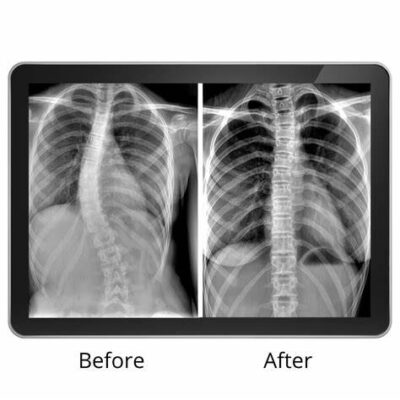

Understanding Lumbar Scoliosis XRays: Key Insights into Spinal Deformities